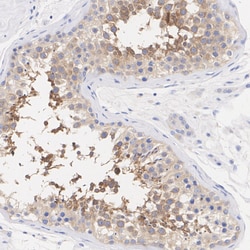

Positive Control: K-562 cell lysate, Jurkat cell lysate, HEK-293 cell lysate, COS-1 cell lysate, Mouse brain tissue lysate, Mouse testis tissue lysate, Rat testis tissue lysate, human testis tissue, mouse testis tissue, rat testis tissue.Tissue Specificity: Low tissue specificitySubcellular Location: Nucleus, Cytoplasm, Membrane, Mitochondrion.Sequence Similarities: 92% Mouse/RatPredicted band size: 49 kDa.

| Immunohistochemistry (Paraffin), Immunoprecipitation, Western Blot | |